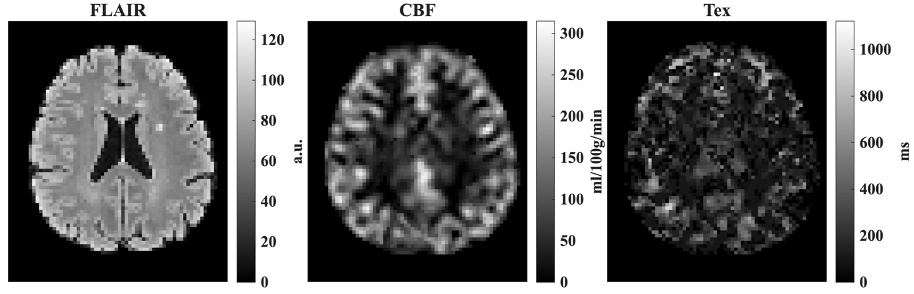

Figure 1 exhibits a Fluid attenuated inversio recovery (FLAIR) image, cerebral blood flow (CBF) and time of exchange (Tex) maps of a healthy volunteer while Figure 2 shows a person with MS (pwMS). In the preleminary results, increased CBF values at the lesions than normal appearing white matter (NAWM) was observed in patients wtih MS. Overall, the Tex values of NAWM were lower than those of lesions in pwMS.

Figure 1 FLAIR, CBF and Tex maps of a volunteer